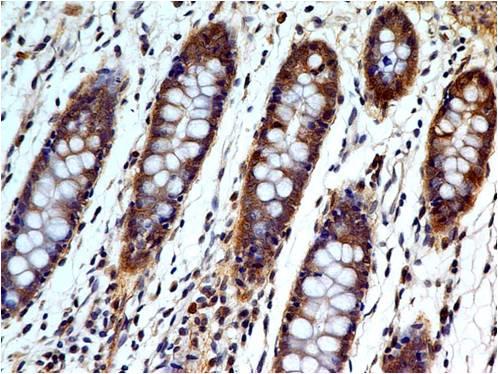

Figure 1: Anti-Involucrin antibody(39-1063). IHC(P): Human Lung Cancer Tissue.

Western blot : 2μg/ml; Immunohistochemistry(Paraffin-embedded Section) : 0.4-1μg/ml; Immunohistochemistry(Frozen Section) : 0.4-1μg/ml; Immunocytochemistry : 1μg/ml

| Tissue Specificity: | Keratinocytes of epidermis and other stratified squamous epithelia. |